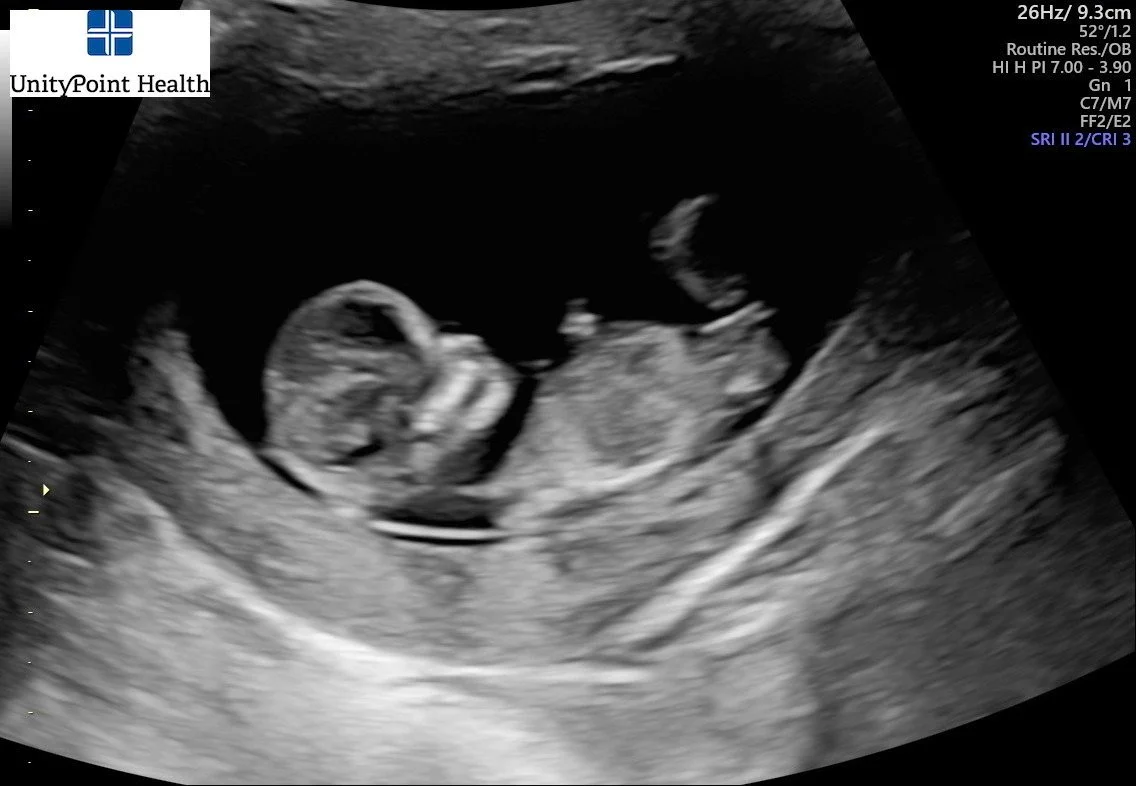

In my 12-week appointment today, the doctor reassured me in several ways and gave me some really great facts to stick to:

-I am an AMA (Advanced Maternal Age) pregnancy (meaning I’m over 35). And they don’t let an AMA go past 39 weeks. For context, Adelaide was born at 39w5d and Loch was born at 37w6d, both were induced for different reasons. This policy confirmed that I need to be done with summer photo sessions by July 1.